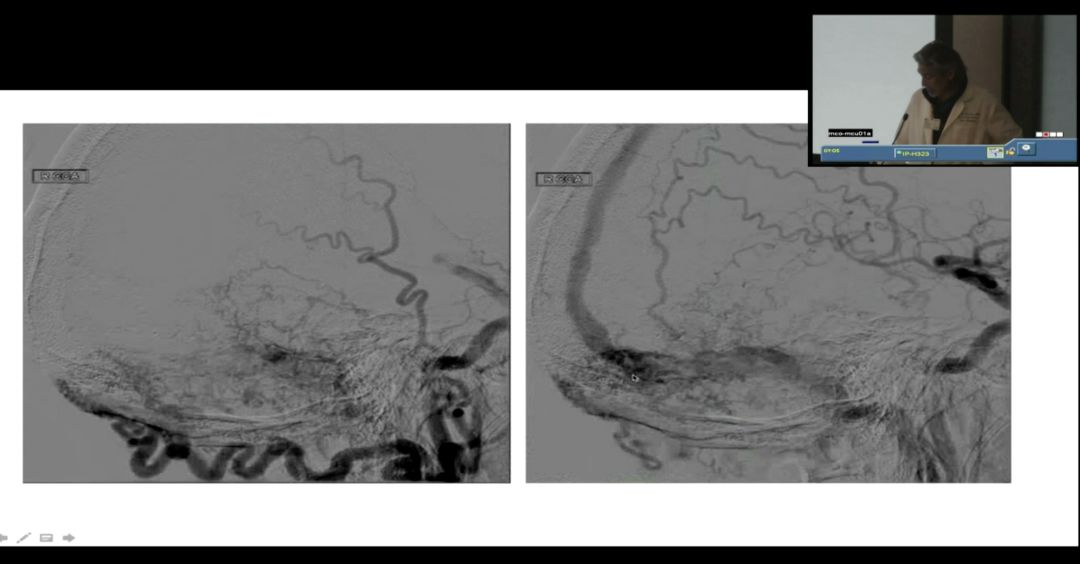

来自UCLA介入治疗的主任Gary Duckwiller教授将一例窦汇区复杂硬脑膜动静脉瘘进行了讨论,由于该病人的动静脉瘘位于窦汇横窦区,而且为多瘘口的复杂型瘘,对于这例病人UCLA的介入团队已经进行了两次手术,第一次采用了经动脉入路的治疗方案,术中采用了Scepter C球囊来阻断ONYX胶的反流,将一部分的瘘口闭塞,瘘的血流量得以下降,但是仍然有横窦的逆向引流,二次手术在横窦和乙状窦中置入支架,来缓解静脉窦的逆向血流。

通过二次手术后的影像来看,患者的逆向血流明显的好转,症状也有明显的改善,但是仍有没有闭塞的瘘口,所以该患者还需要进行第三次手术。对于这例复杂的病例,浙医二院的介入团队提出在第一次治疗时是否适合采用经静脉入路,以及如果采用了动脉入路是否再静脉窦中放置球囊更为安全,对于这些治疗的细节双方团队深入交换了彼此的意见。